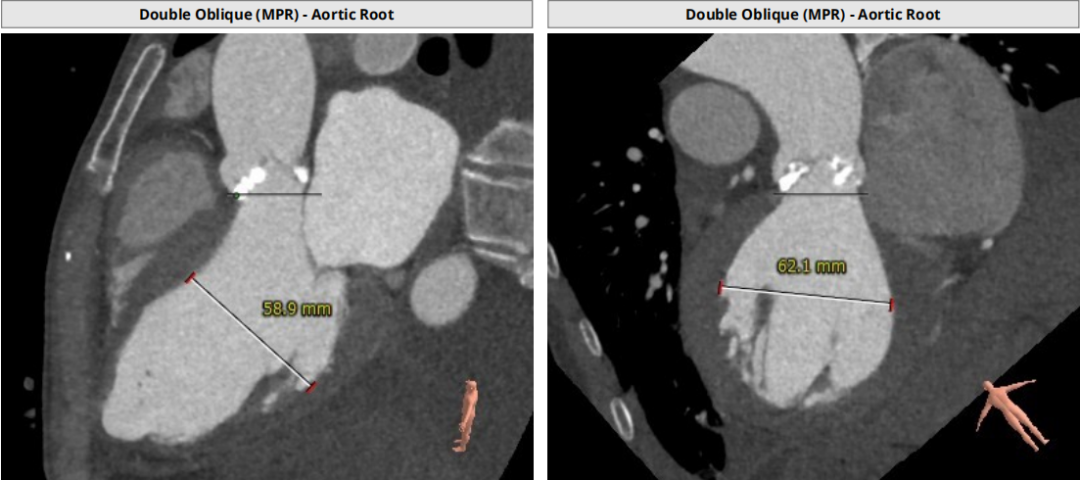

类TYPE2型二叶瓣,极重度钙化,左冠高度稍低,右冠高度可,升主动脉增宽,最宽处约40mm,心脏角度不大,左室大,心尖部局部心肌薄弱作。

1.瓣膜选择:瓣环径24mm,但属于type2型二叶瓣,钙化范围广、程度重,球囊选择18,根据预扩结果进一步明确瓣膜型号,备L23/26/29。

2.冠脉风险:瓣叶较长,右冠高度尚可,左冠9.3mm偏低,但由于钙化分布广且重,瓣叶可能不会被推挤到冠脉开口,术中根据球扩进一步明确。